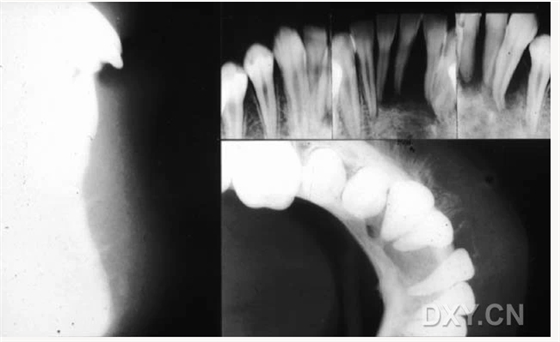

涎石病